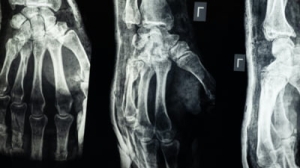

Cercetătorii chinezi susțin că au dezvoltat un adeziv osos care poate fi folosit pentru a trata fracturile și fragmentele osoase zdrobite, printr-o procedură care durează doar trei minute.

Substanța, denumită „Bone-02", promite să repare fragmentele de os în doar câteva minute, reducând necesitatea intervențiilor chirurgicale invazive și a implanturilor metalice.

Inspirat de modul în care stridiile aderă ferm la suprafețe sub apă, echipa a încercat să reproducă acest mecanism pentru a fixa oasele fracturate. Potrivit dr. Xianfeng, adezivul reușește o fixare precisă în două-trei minute, chiar și într-un mediu bogat în sânge, situație întâlnită în timpul intervențiilor chirurgicale.

În testele de laborator și în primele încercări clinice, substanța a demonstrat atât siguranță, cât și eficacitate, potrivit echipei. Într-un studiu, procedura a fost finalizată în mai puțin de trei minute, comparativ cu tratamentele convenționale care implică incizii mari și fixare cu plăci și șuruburi metalice.

Formula combină compuși de calciu și proteine specifice care asigură o legătură puternică, flexibilă și sigură. Aplicarea sa necesită doar o incizie minimă, prin care adezivul este introdus direct în zona fracturată, sigilând fragmentele osoase în câteva minute.

Până în prezent, „Bone-02" a fost testat cu succes la peste 150 de pacienți, potrivit presei chineze. Forța de lipire a oaselor a depășit 180 de kilograme, iar parametrii mecanici (rezistența la forfecare și la compresie) sugerează că adezivul ar putea înlocui, în viitor, implanturile metalice tradiționale. În plus, cercetătorii susțin că metoda ar putea reduce riscurile de reacții adverse și infecții post-operatorii.